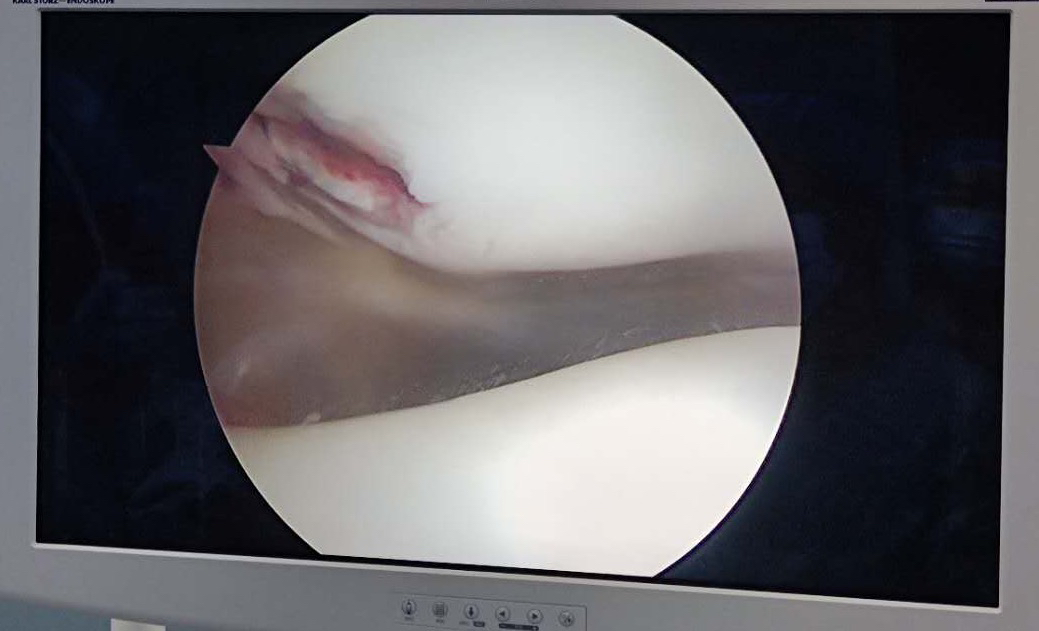

髌骨脱位造成髌骨内下极骨软骨骨折 需要CT检查 可以看见关节内游离骨片 (这是绝对需要早期手术的!)